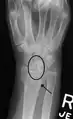

X-ray images indicate scapholunate ligament instability when the scapholunate distance is more than 3 mm, which is called scapholunate dissociation.[7] A static scapholunate instability is generally readily visible, but a dynamic scapholunate instability can only be seen radiographically in certain wrist positions or under certain loading conditions, such as when clenching the wrist, or loading the wrist in ulnar deviation.[6]

In order to diagnose a SLAC wrist you need a posterior anterior (PA) view X-ray, a lateral view X-ray and a fist view X-ray.[8] The fist X-ray is often made if there is no convincing Terry Thomas sign. A fist X-ray of a scapholunate ligament rupture will show a descending capitate bone. Making a fist will give pressure at the capitate, which will descend if there is a rupture in the scapholunate ligament.